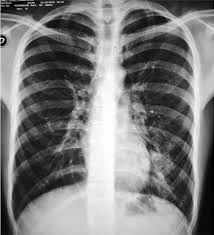

“Tuvimos algunas situaciones muy poco frecuentes. Uno de los ejemplos es un cuera que sufrió un síndrome de Guillain-Barré, que es una complicación descripta, pero muy rara. Sacando eso, no hemos registrado complicaciones no habituales. Lo que sí hemos tenido ahora, pero que no se relaciona con el dengue, son las neumonías atípicas y en formas bastante graves. No es un número muy alto, pero hemos tenido citacosis con mucha destrucción pulmonar”, informa.